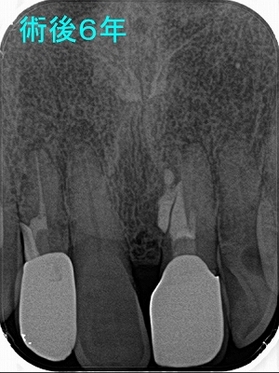

今月撮らせてもらったレントゲン

右上2:は骨頂からレジンで立ち上げましたが、問題は出ていません。

左上1:はMTAセメントが歯の輪郭に沿って割れていますが、今の所異物反応は出ていません。

こういうレントゲンを見ると、歯って咬む力で動いているんだなと改めて覚えさせられます。

患者さんも「先生調子いいよ!」と言ってくれていますので経過観察で行きます。